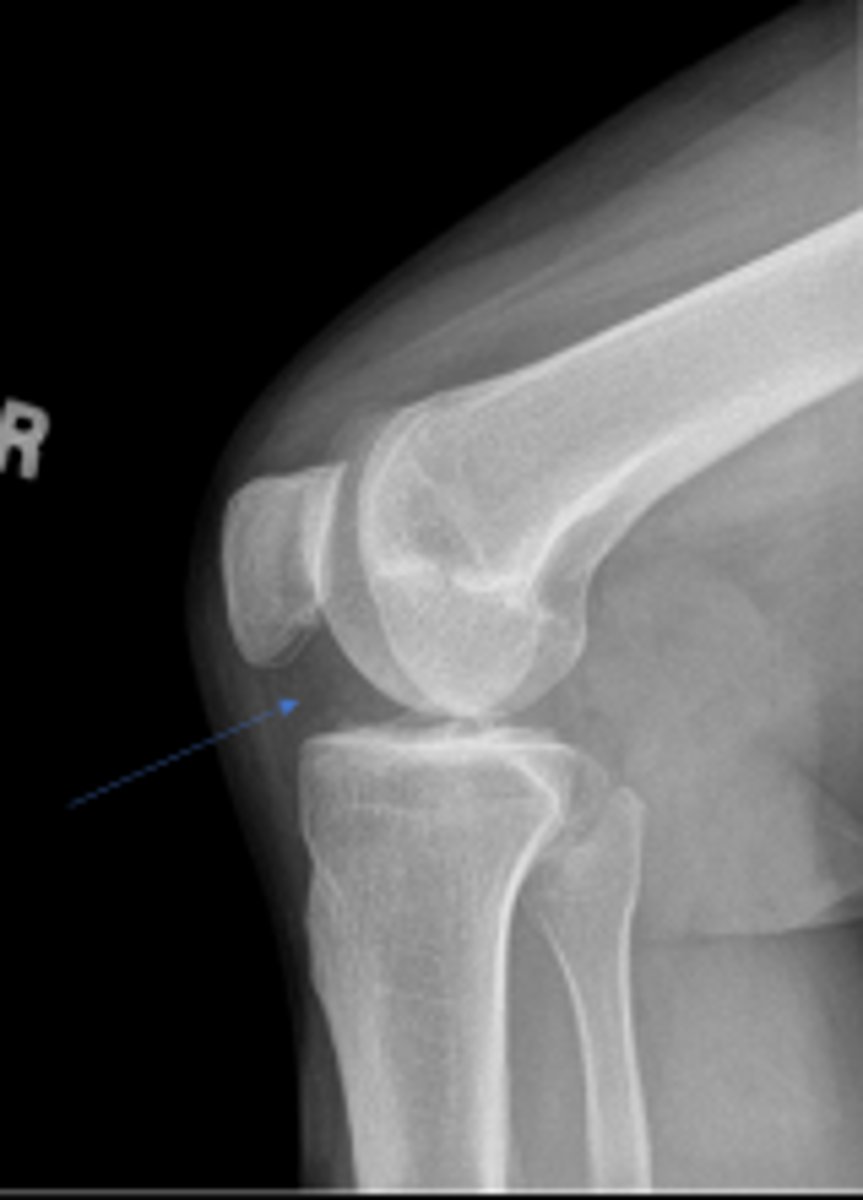

Neck of the fibula

What are the blue arrows pointing to?

Ludloff's space/triangle

What are the red arrows pointing to?